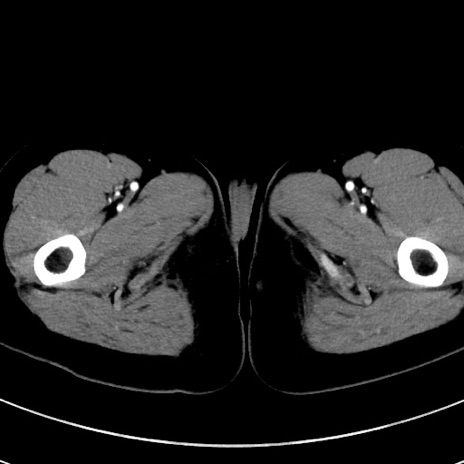

症例17(横断像)

【症例】20歳代女性

【主訴】嘔吐、下腹部痛

【現病歴】昨日夕食後に嘔吐し下腹部痛が出現。本日になっても嘔吐持続し改善しないため来院。

【身体所見】意識清明、BT 37.2℃、BP 108/67mmHg、腹部:平坦、やや硬、下腹部正中から右にかけて圧痛あり、反跳痛軽度あり、tapping pain(+)。

【データ】WBC 13600、CRP 14.94